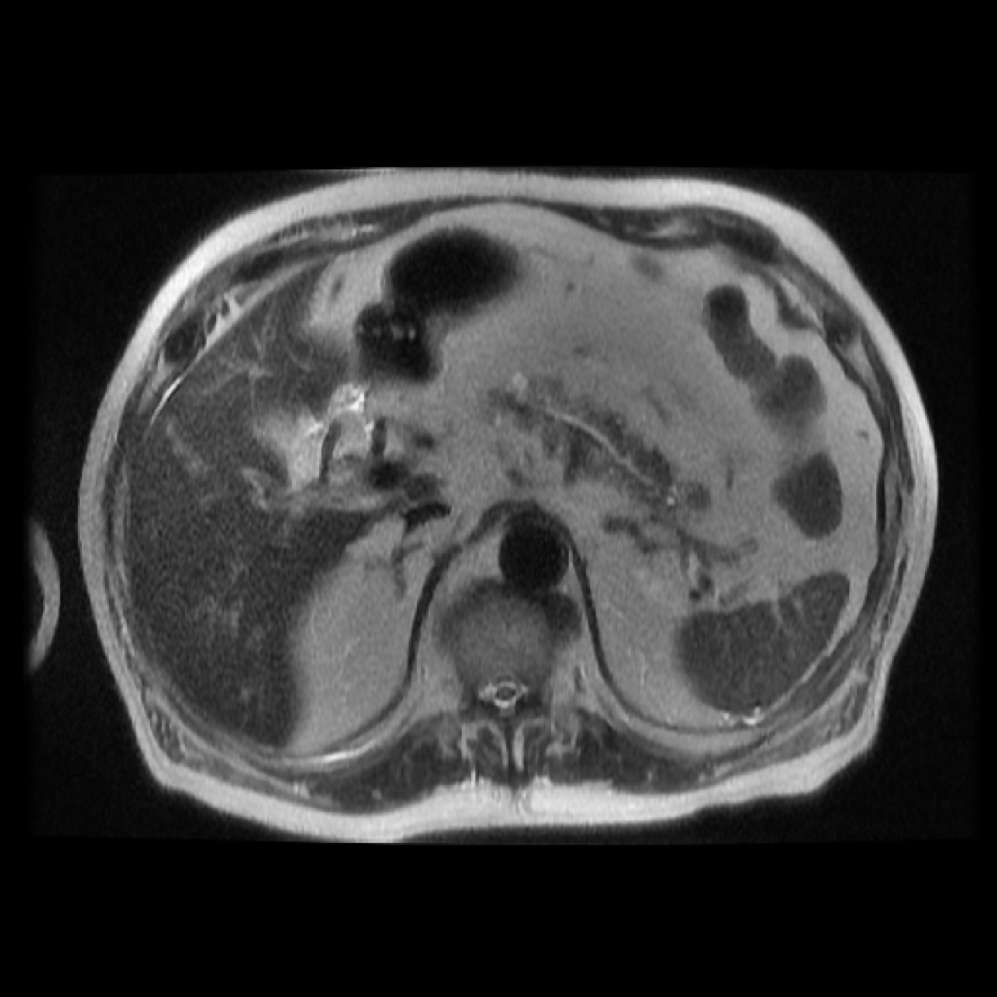

Each patient was categorized into one of these three ground truth classes: no risk/control, IPMN low-risk, or IPMN high-risk. To evaluate variability in image acquisition, we applied uniform manifold approximation and projection (UMAP) to image quality indicators, revealing distinct clustering patterns by imaging center and slice thickness. This heterogeneity reflects real-world clinical variability, enhancing the dataset’s generalizability while presenting technical challenges for model development. Fig. 6 shows examples of low-grade, high-grade, and cancer developing IPMNs from the Cyst-X dataset.

Accurate pancreas segmentation is a critical prerequisite for precise cyst analysis and classification. Recently, we developed PanSegNet [zhang2025large], a novel segmentation architecture incorporating linear self-attention layers [zhang2022dynamic] within the nnUNet framework [isensee2021nnu] to enhance global information modeling capabilities while maintaining computational efficiency (Fig. 1). PanSegNet demonstrated exceptional segmentation performance across both T1W and T2W modalities, achieving mean dice scores of 86.817.30% and 89.626.38%, respectively (Table 1, Fig. 2b-c). This performance significantly exceeded that of Swin-UNETR [hatamizadeh2021swin], one of the most used state-of-the-art transformer-based medical segmentation models, which achieved dice scores of 79.091.40% and 76.290.66% for T1W and T2W, respectively (). In this study, we integrated PanSegNet into our Cyst-X engine along with a classifier for risk prediction. In Section 2.2, we show that the choice of segmentation model affects the classification results. The performance advantage of PanSegNet was consistent across all seven medical centers, demonstrating robust generalization despite variations in imaging protocols and equipment (Table 1). This cross-institutional reliability is particularly important for clinical applications, where model performance must remain consistent regardless of imaging site or acquisition parameters.